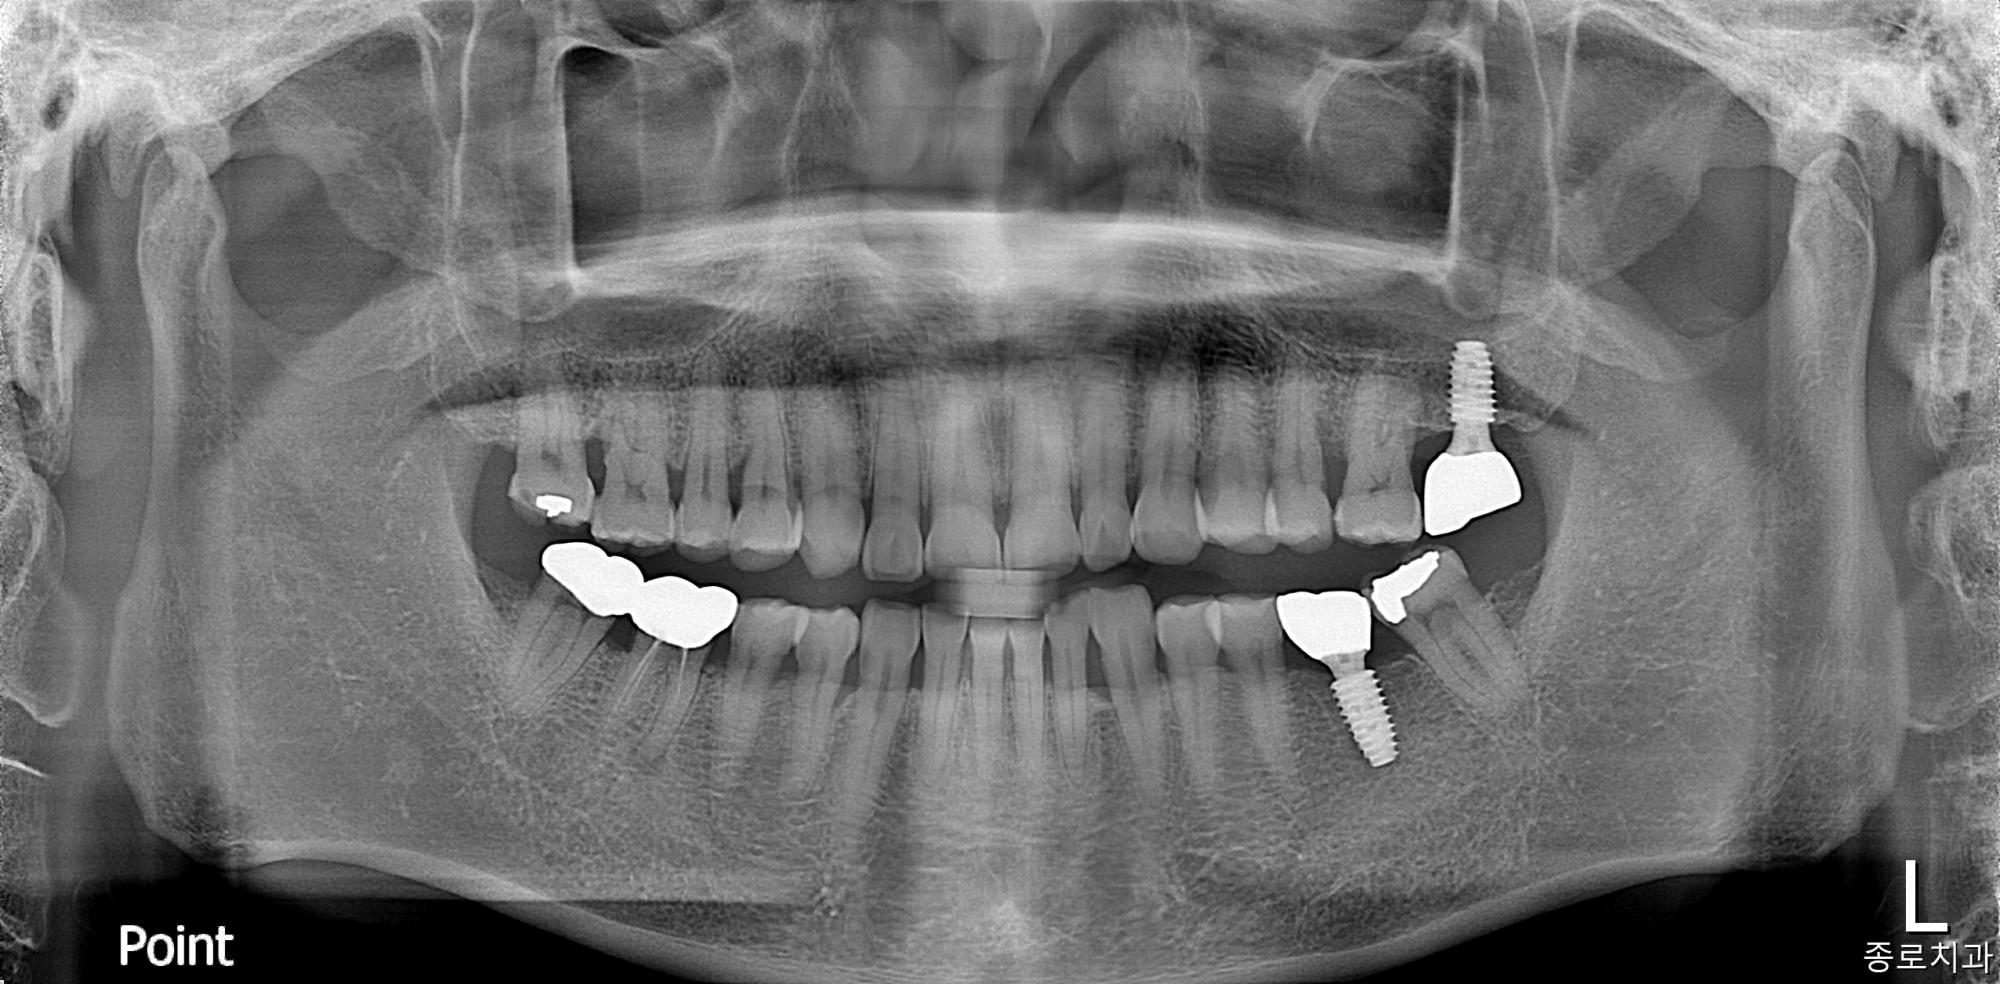

임플란트

치료 전

치료 후